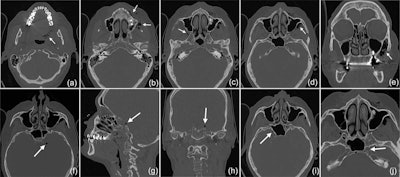

Due to the strange sensations reported by the patient and unclear clinical signs, the patient underwent a CT scan, which showed the development of a subcutaneous emphysema. The air spread from the facial aspect in caudal and cranial directions. Air was also detected in the left carotid canal and intracranially, according to the report.

A CT scan revealed that the subcutaneous emphysema extended to the woman's left side pharyngeal (a) and facial (b) into the right (c) and left (d) pterygopalatine fossa, with a maximum extension of up to 3 cm on the left side (e). The intracranial air bubbles reached a diameter of up to 5 mm (axial [f], sagittal [g], and coronal [h] view). The bubbles were detected on both sides of the sella turcica in the region of the cavernous sinus (i) and on the left side in the carotid canal (j). Images courtesy of Bruckmann et al. Licensed by CC BY 4.0.